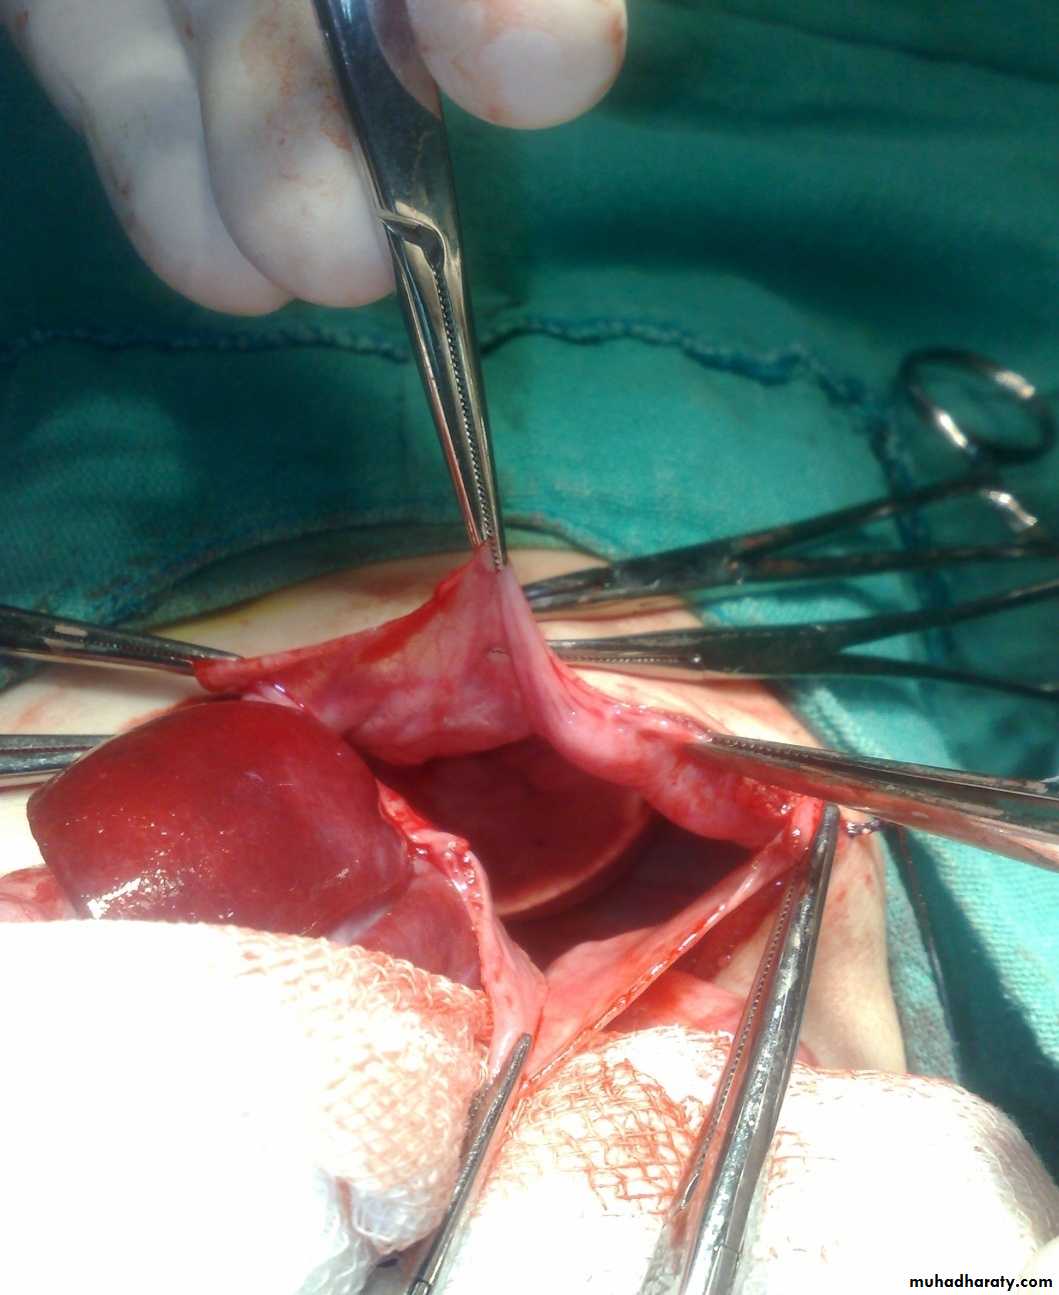

The Child with an Abdominal Mass

Pediatric surgery practical